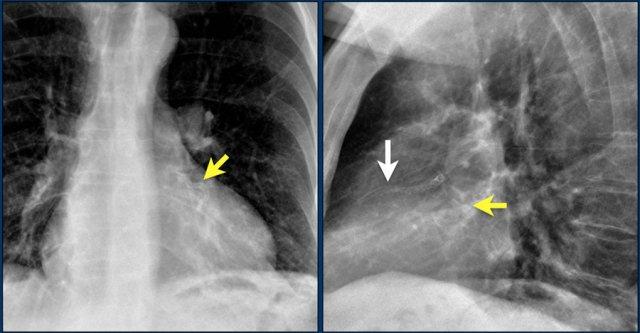

Các hình ảnh cho thấy máy tạo nhịp tim với điện cực nhĩ và điện cực thất.

Đầu điện cực nhĩ hướng lên trên và ra trước, vì vị trí lý tưởng là trong tiểu nhĩ phải, nơi điện cực được neo chặt vào các bè cơ thô.

Đầu điện cực thất được đặt tại mỏm thất phải, vị trí này nằm ở bên trái cột sống trên phim X-quang ngực thẳng và ở phía trước trên phim chụp nghiêng.

Hình ảnh bên trái cho thấy bệnh nhân có ICD được đặt đúng vị trí.

Vài tháng sau, thiết bị hoạt động không bình thường do hộp ICD và điện cực bị xoay (mũi tên vàng) và co rút lại (mũi tên trắng).

Đây là một bệnh nhân khác mắc hội chứng Twiddler.

Lưu ý hình ảnh điện cực bị cuộn xoắn gần máy tạo nhịp và tại đầu điện cực trong thất phải (mũi tên).